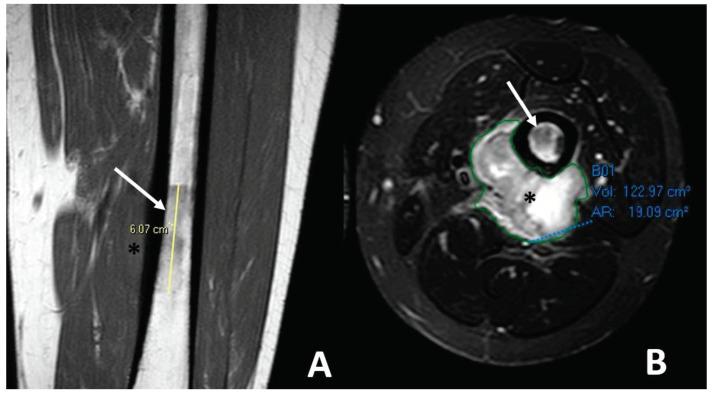

Osteosarcomas are rare malignancies (<1% of all cancers) that produce an osteoid matrix. Osteosarcomas are the second most frequent type of primary bone tumor after multiple myeloma and the most prevalent primary bone tumor in children. The spectrum of imaging findings of these malignancies varies significantly, reflecting different histological subtypes. For instance, conventional osteosarcoma typically presents with a mixed radiological pattern (lytic and bone mineralization) or with a completely eburneous one; aggressive periosteal reactions such as sunburst, Codman triangle, and soft-tissue components are frequently displayed. On the other hand, telangiectatic osteosarcoma usually presents as a purely lytic lesion with multiple fluid-fluid levels on MRI fluid-sensitive sequences. Other typical and atypical radiological patterns of presentation in other subtypes of osteosarcomas are described in this review. In addition to the characteristics associated with osteosarcoma subtyping, this review article also focuses on imaging features that have been associated with patient outcomes, namely response to chemotherapy and event-free and overall survivals. This includes simple semantic radiological features (such as tumor dimensions, anatomical location with difficulty of radical surgery, occurrence of pathological fractures, and presence of distant metastases), but also quantitative imaging parameters from diffusion-weighted imaging, dynamic contrast-enhanced MRI, and 18F-FDG positron emission tomography and radiomics approaches. Other particular features are described in the text. Overall, this comprehensive literature review aims to be a practical tool for oncologists, pathologists, surgeons, and radiologists involved in these patients' care.

骨肉瘤是一种罕见的恶性肿瘤(占所有癌症的比例不到1%),可产生类骨质基质。骨肉瘤是继多发性骨髓瘤之后第二常见的原发性骨肿瘤类型,也是儿童中最常见的原发性骨肿瘤。这些恶性肿瘤的影像学表现谱差异很大,反映了不同的组织学亚型。例如,传统骨肉瘤通常表现为混合性放射学模式(溶骨性和骨矿化)或完全骨化模式;常显示侵袭性骨膜反应,如日光放射状、科德曼三角和软组织成分。另一方面,毛细血管扩张性骨肉瘤通常表现为纯溶骨性病变,在MRI液体敏感序列上有多个液-液平面。本文综述了骨肉瘤其他亚型的其他典型和非典型放射学表现模式。除了与骨肉瘤亚型相关的特征外,本文还重点关注与患者预后相关的影像学特征,即对化疗的反应、无事件生存期和总生存期。这包括简单的语义放射学特征(如肿瘤大小、根治性手术困难的解剖位置、病理性骨折的发生以及远处转移的存在),也包括扩散加权成像、动态对比增强MRI、18F-FDG正电子发射断层扫描和放射组学方法的定量成像参数。文中还描述了其他特殊特征。总体而言,这篇全面的文献综述旨在成为参与这些患者护理的肿瘤学家、病理学家、外科医生和放射科医生的实用工具。